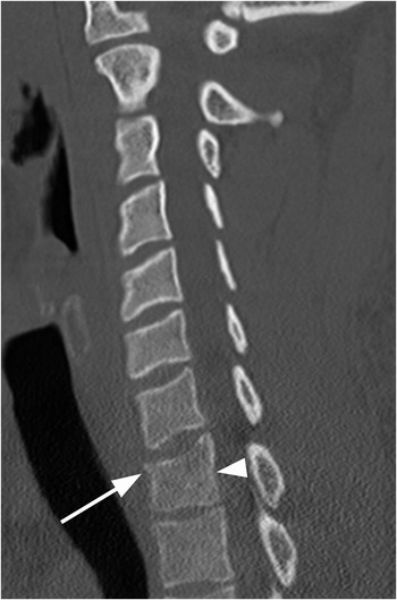

Thoracic Spine Disorders